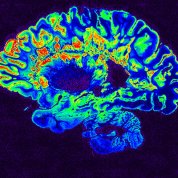

Brain scan image colored blue with several areas highlighted in green and orange

On the Cover

A pseudo-colored image of a high-resolution gradient-echo MRI scan of a fixed cerebral hemisphere from a person with multiple sclerosis

Govind Bhagavatheeshwaran & Daniel Reich/NINDS